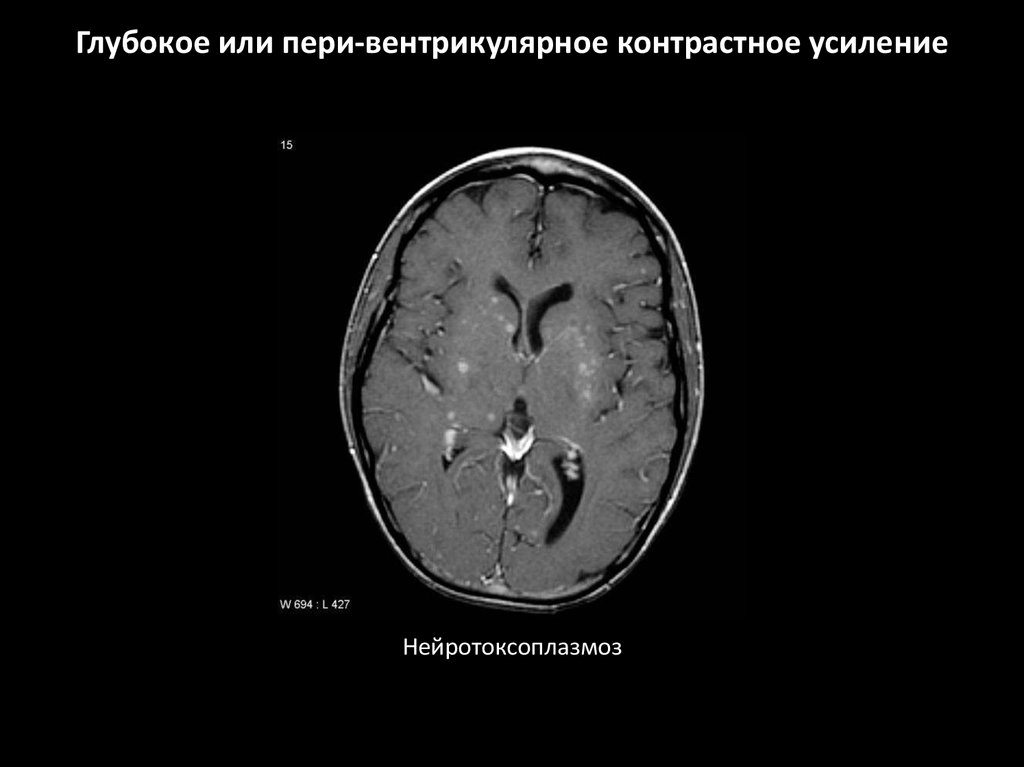

Глубокое или пери-вентрикулярное контрастное усиление

Особенности:

• Расположены в глубоком белом веществе

и сером (например в базальных ганглиях,

таламусе)

Наблюдается при:

• Метаболическое поражение

• Лейкоэнцефалопатии

• Токсоплазмоз \ лимфома

(иммунокомпрометированные пациенты)

Нейротоксоплазмоз